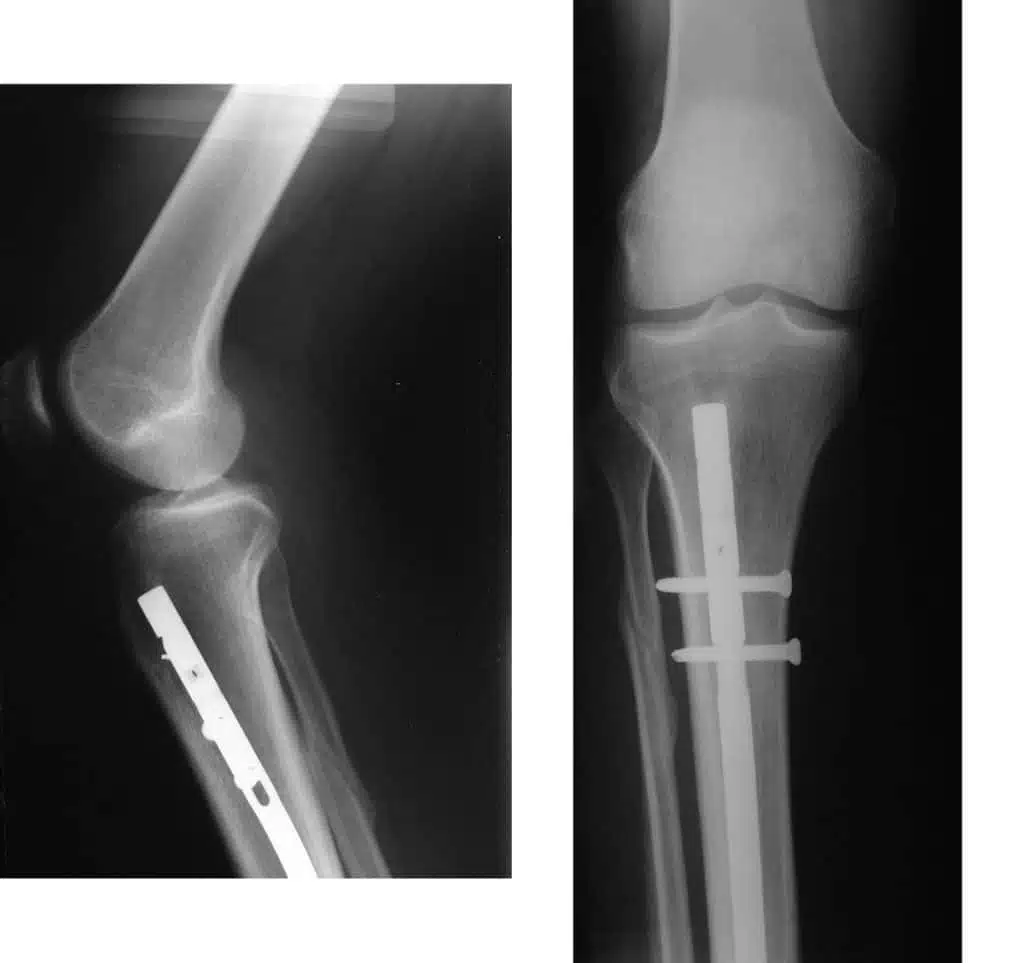

عملية مسمار النخاع تعتبر من أفضل الطرق العلاجية التي يمكن الاستعانة بها في حالة وجود كسور شديدة في الساق، وهي تتم من خلال عدة خطوات، وهي:

- قبل العملية بوقت قصير لابد من تحديد نوع المخدر الذي سيتم تخدير المريض به والذي في العادة يكون كلي.

- يقوم الطبيب بتحديد المنطقة التي تعاني من مشكلة في الساق أو الفخذ ويقوم بتعقيمها.

- يبدأ الطبيب بشق عدد من الثقوب الصغيرة من أجل رؤية المشكلة من الداخل.

- في العادة قد يستخدم الطبيب المنظار به كاميرا صغيرة ويدخله من خلال الثقوب لتحديد الكسور.

- يزيل الطبيب الجراح جميع الأجزاء التالفة في المنطقة ويبدأ بتثبيت المسمار النخاعي بين العظام بعد تحديدها.

- بعد التأكد من ثبات العظام ومرونتها يبدأ الطبيب من غلق تلك الثقوب بخياطة من الغرز الطبية.

- يكون المريض تحت رعاية الطبيب على الأقل لمدة 48 ساعة للتأكد من عدم وجود أي مضاعفات.